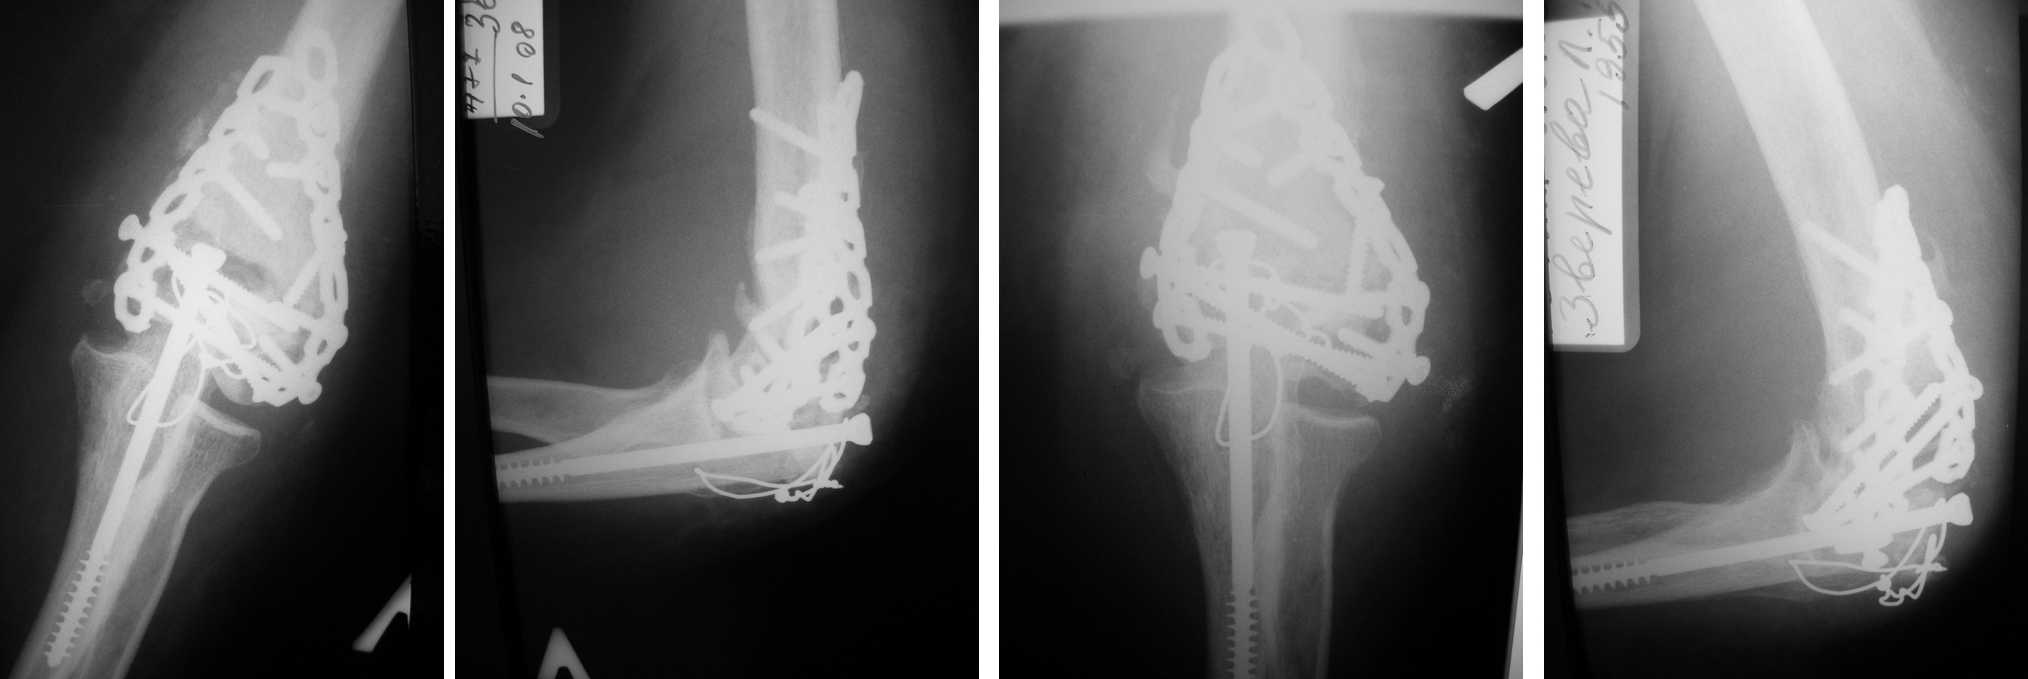

Уважаемые коллеги! Обратилась за помощью пациентка с жалобами на боль при нагрузке, ограничение движений, чувство жара в области левого локтевого сустава и увеличение его в объеме. Из анамнеза: травма в результате ДТП 09.08.07. В сентябре выполнена 2007 выполнена операция накостного металоостеосинтеза, после заживления ран выписана на амбулаторное лечение по месту жительства (к сожалению первоначальные снимки и снимки непосредственно после операции на руки отданы не были). Далее лечилась амбулаторно по месту жительства. В связи с вышеперечисленными жалобами имея на руках предоставленные снимки обратилась ко мне на прием. Объективно: Контуры локтевого сустава сглажены, объем +1,5 см., температура пальпатолно – повышена, отмечается легкая гиперемия параартикулярных тканей. При пальпации боль умеренная (ВАШ – 5-6 баллов, в покое до 3), слышен «хруст». Объем движений сгибание – 80 гр., разгибание 160 гр.. Пункция сустава – отделяемого нет. Из лабораторных данных: СОЭ 18, лейкоциты 9,8 без сдвига, остальное в пределах нормы. Вопрос состоит в следующем: что с этим делать? То, что остеосинтез не состоятелен – понятно, но стоит ли оперировать сейчас, или дать внешнюю иммобилизацию и ждать консолидации оставив все как есть?А может у кого-то ест и другие предложения? Буду благодарен за любые советы.

Уважаемый Николай Петрович, Вы имеете дело с консолидированным, судя по представленным Ргр, переломом дистального плеча, очевидно, типа С. Вернее, имеете дело с пациенкой, перенесшей данное повреждение. Мне кажется этот остеосинтез вполне состоятельным, иначе, при таком объёме движений, миграция конструкций была бы неизбежной. А этого мы не видим. Мне бы казалось очень важным, если есть такая возможность. проконсультировать пациентку в той клинике, а лучше у того хирурга, у которого она оперировалась. И вместе вы примете оптимальное для пациенки решение. Ведь, зачастую, нержавеющую сталь лучше удалить быстрее, чем титан, особенно если есть местная тканевая реакция, конструкции от невнятного производителя тоже не следует долго сохранять и тд. Но решить Вы это сможете в кооперации с оперировавшим хирургом. Если же возможности обсудить ситуацию по тем или иным причинам нет, то я бы склонился к удалению конструкций. Но, чего нельзя делать категорически, с моей точки зрения, так это применять внешнюю иммобилизацию и физиолечение. Движения будут потеряны с большой долей вероятности. И ещё раз повторюсь, считаю очень важным проконсультировать больную у оперировавшего хирурга. С уважением, Волна

Здравствуйте! Уважаемый Андрей Волна, я абсолютно с вами соглашусь в отношении консультации с оперировавшим хирургом, но в этом есть свои сложности - в ближайшее время она врядли сможет туда выехать, это другой регион, да и расстояния значительные. Я понимаю, что качество снимков желает быть лучше, но всетаки, если присмотреться, миграция есть и уменьшение плотности кости с уменьшением размеров мыщелков - тоже есть.

Повышенное СОЭ в течение шести и более месяцев после внутрисуставных оперированных переломов и при отсутствии другого воспалительного очага в организме вызывает подозрение на инфекционный процесс.

Имеющиеся другие клинические признаки, местная температура, отсутствие эффекта на фоне противовоспалительной терапии, вместе улучшения появления болей в 2.5-3 месяцев также наводит на подозрение на несостоятельность остеосинтеза с инфицированием. Характерный “хруст” отошедших от пластины шурупов подтверждает подозрение.

Насчет консолидации трудно ответить, для определения сращения нужно в различных ракурсах сделать рентген снимки или КТ, возможно как-то удастся пробить костное окно через ренгенологически отраженный "блеск".

Операция по ревизии подтвердит консолидацию и наличия инфекции. На всякий случай надо быть готовым к инфицированному ложному суставу, т.е. дальнейшими промываниями и антибиотическим бусам.